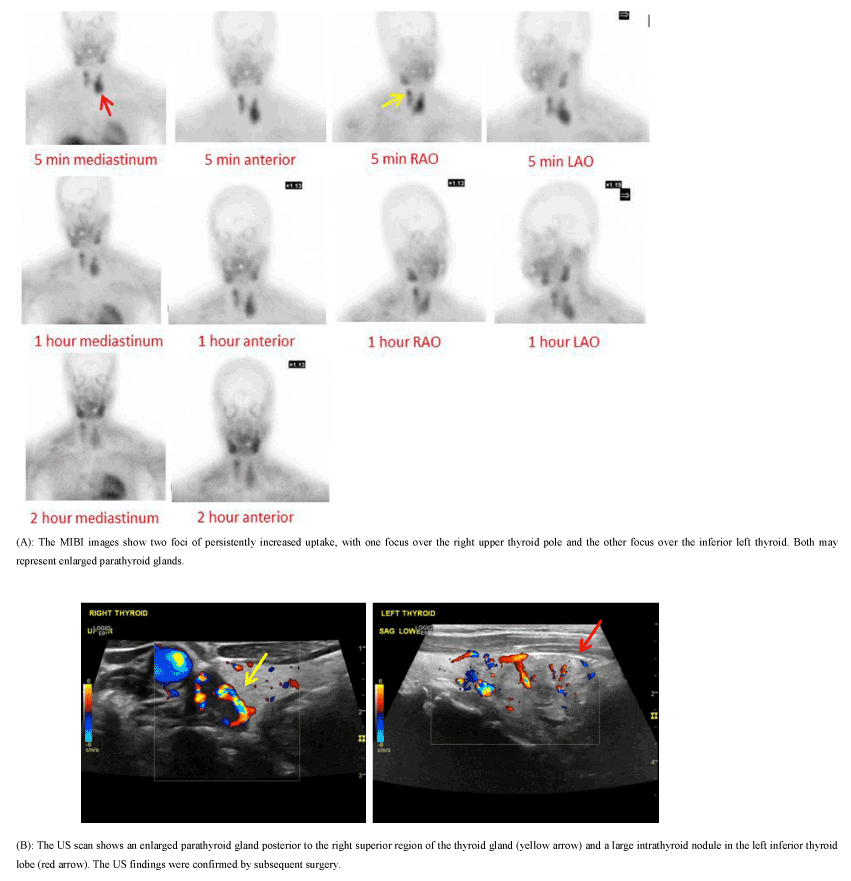

Figure 2. 49-year-old female presented with a PTH level of 1123.5 pg/ml and a calcium level of 12.8 mg/dl.